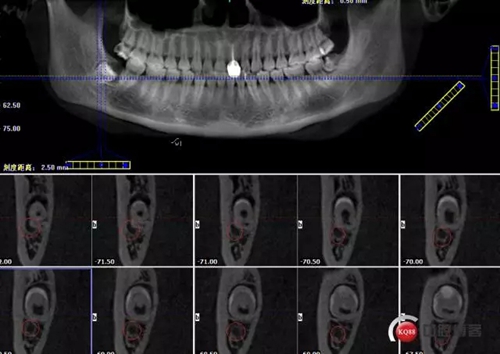

1498615723_447506.png

牙齒上1/3CT切片,神經(jīng)管在下方

1498615726_560454.png

牙齒中1/3神經(jīng)管偏頰側(cè)